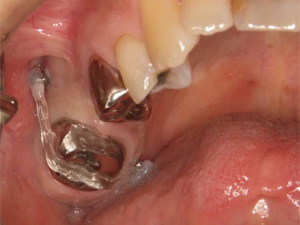

裁断済みとなっております。書き込み、マーカー等はございません。大きな目立った汚れはございません。- 著者: HYO-SANG PARK- 監修: 加藤直美- タイトル: アンカースクリューを用いた新しいMTM矯正- 内容: 補綴前矯正に関する技術と事例- 出版社: 永末書店ご覧いただきありがとうございます。月星歯科